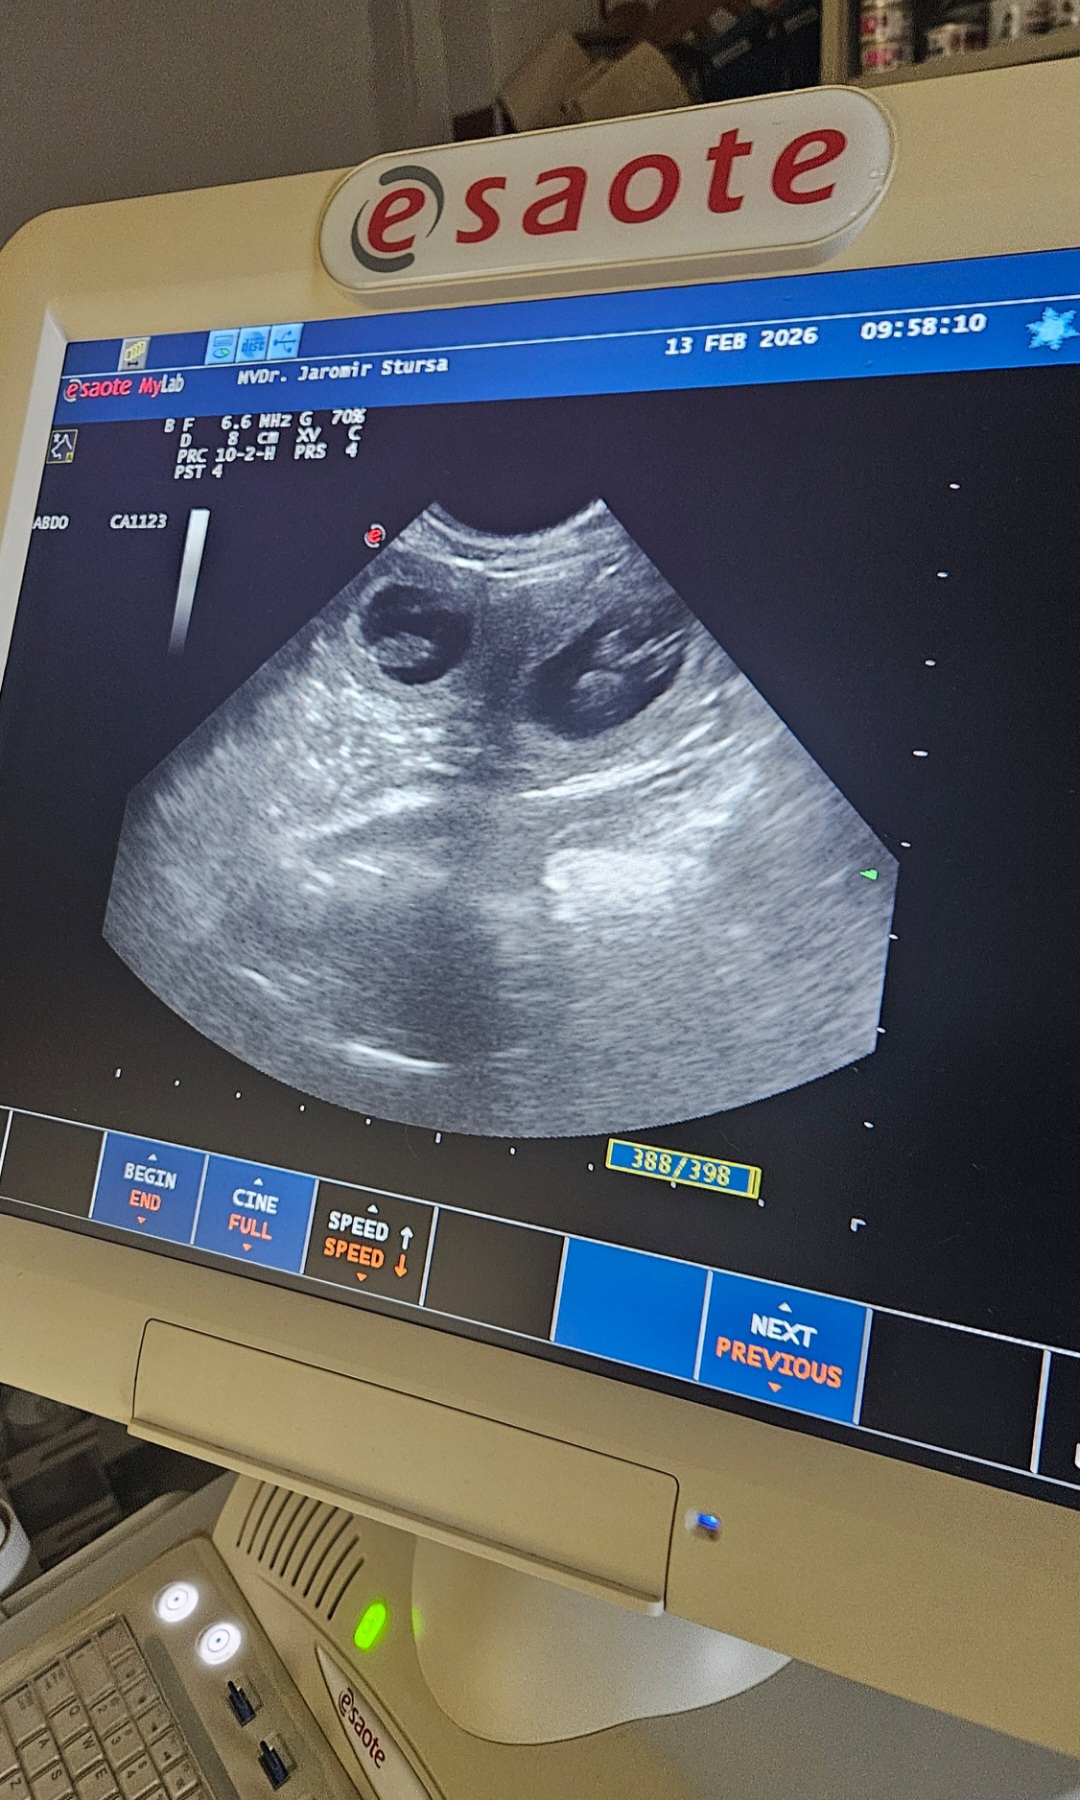

UTZ 13. 02. 2026

Grace

43. den březosti